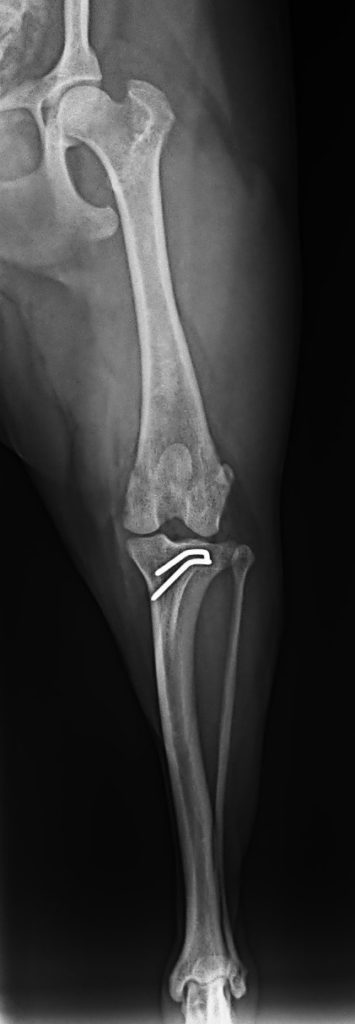

- 膝蓋骨脱臼(パテラ)

・膝蓋骨脱臼整復術 30万円前後